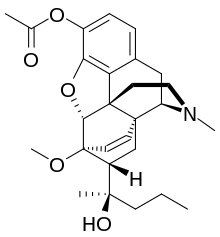

Oripavine derivatives

Thienorphine

- 7-PET

- Acetorphine

- Alletorphine (N-allyl-noretorphine)

- BU-48

- Buprenorphine

- Buprenorphine-3-glucuronide

- Cyprenorphine

- Dihydroetorphine

- Etorphine

- Homprenorphine

- 18,19-Dehydrobuprenorphine (HS-599)

- N-cyclopropylmethylnoretorphine

- Nepenthone

- Norbuprenorphine

- Norbuprenorphine-3-glucuronide

- Thevinone

- Thienorphine

Structures

| Oripavine derivatives | ||||

|---|---|---|---|---|

7-PET 7-PET |

Acetorphine Acetorphine |

Alletorphine Alletorphine |

BU-48 BU-48 |

Buprenorphine Buprenorphine |

Cyprenorphine Cyprenorphine |

Dihydroetorphine Dihydroetorphine |

Etorphine Etorphine |

Homprenorphine Homprenorphine |

18,19-Dehydrobuprenorphine 18,19-Dehydrobuprenorphine |

N-cyclopropylmethylnoretorphine N-cyclopropylmethylnoretorphine |

Nepenthone Nepenthone |

Norbuprenorphine Norbuprenorphine |

Thevinone Thevinone |

Thienorphine Thienorphine |